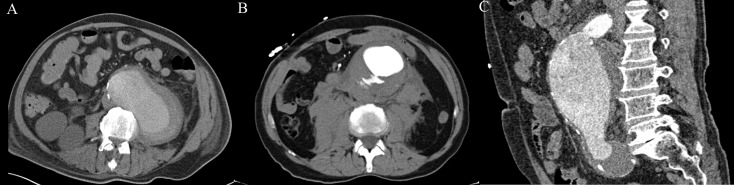

This study has some limitations. In all subjects endovascular infrarenal aneurysm repair was done. Therefore the size of the aAAA was skewed towards the threshold to treat (5.5cm) and thus these AAA already posed a higher risk of rupture. Additionally, the geometries included in this study are geometries suitable for endovascular repair without branches; i.e. an infrarenal AAA with a proper landing zone, sufficient iliac access and limited tortuosity. A quarter of the ruptured geometries analyzed (examples in Fig 4), and two percent of the asymptomatic geometries could not be accurately extracted. Consequently, FEA was not possible. As PWS increases at higher curvatures these cases indicate a possible benefit for the biomechanical analysis over the maximum diameter. However, the segmentation methods should first be optimized to be able to include all cases.

Fig 4. Examples of rAAA cases.

A. AAA and hemorrhagic region could not be distinguished, this case was excluded. B. Contrast extravasation into the ILT, with manual correction a sufficient estimation of pre-rupture state could be acquired. C. Tortuous proximal aneurysm inlet with a decrease in contrast in the aneurysmal lumen and an iliac artery aneurysm, with much manual correction an segmentation could be made.